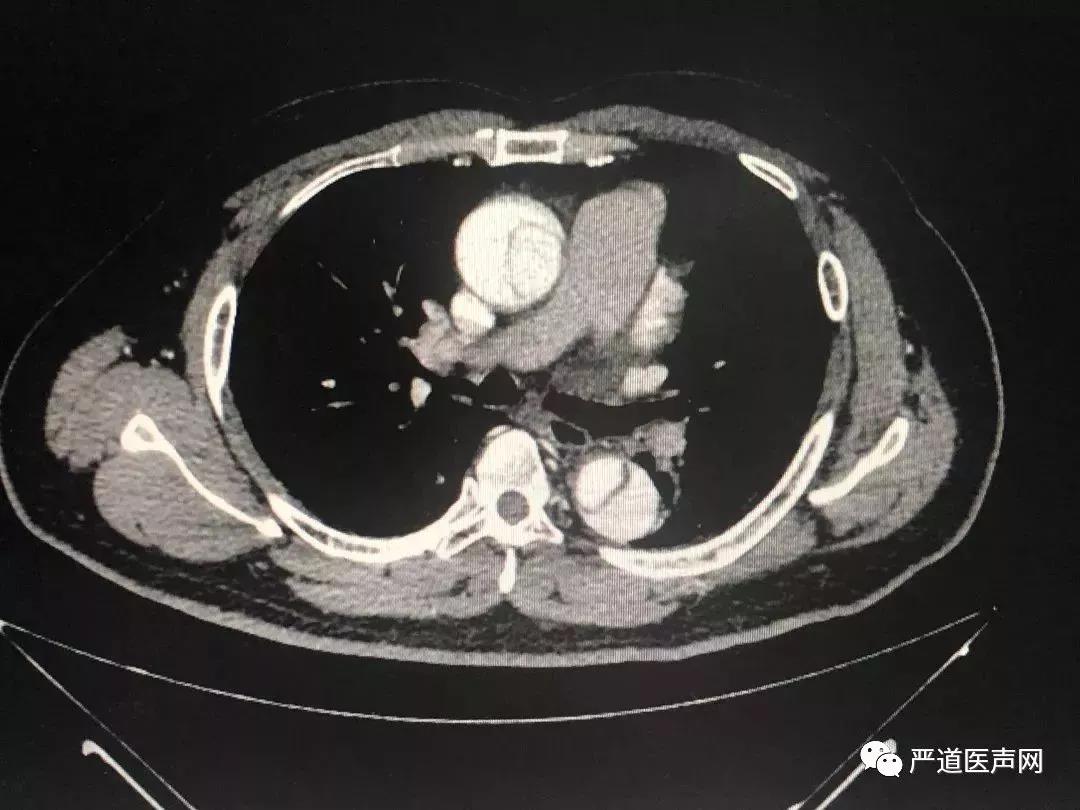

四、冠状动脉CTA检查

考虑到主动脉夹层可能,经猪尾导管行主动脉造影不安全,接下来完成了主动脉CTA检查:

▲主动脉CT提示:自升主动脉根部开始至腹主动脉分出髂动脉之前全段夹层形成

至此,患者胸背痛的原因基本明确:1型主动脉夹层